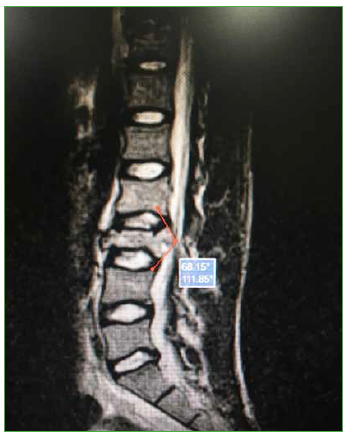

- Ángulo del fragmento retropulsado: medido en cortes sagitales de TC o RM como vértice, el punto del fragmento que impronta sobre el saco y el ángulo que conforman sus límites (Figura 3).

Figura 3.

Resonancia magnética, corte sagital. Ángulo del fragmento retropulsado.